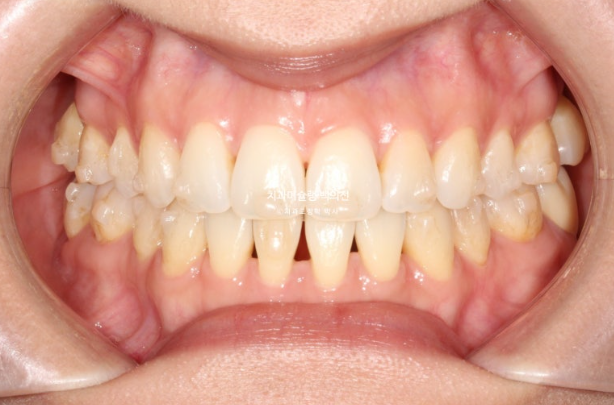

3월부터 5월까지 2달간 7개 장치를 모두 낀 후 모습입니다.

25.05

윗니는 제자리로 잘 들어갔으나 아래 앞니 블랙트라이앵글이 여전히 큽니다.

앞니 배열 완료입니다.

아래 앞니 블랙트라이앵글을 더 없애고자 추가장치 제작에 들어갑니다.